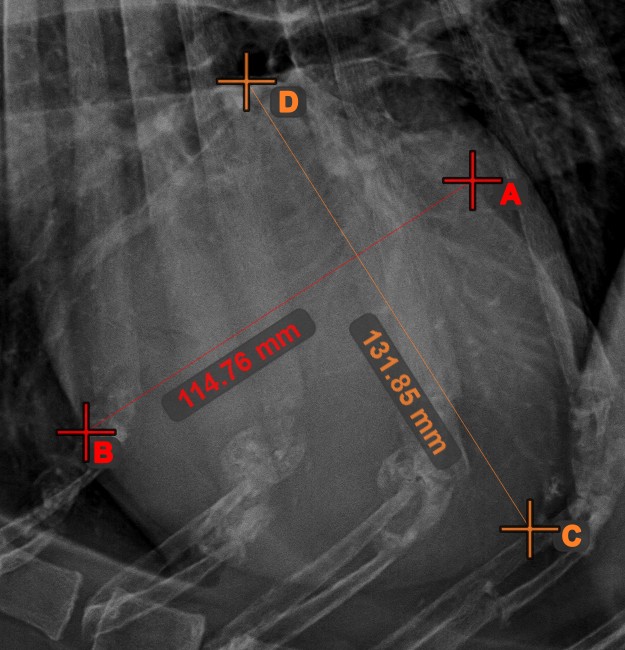

Circle from 3 Points¶

The Circle from 3 Points

tool is a simple and effective way to create a circle from just three points.

Start by selecting the tool from the left toolbar and assign it to one of the available mouse buttons. Place the three points of the circle, or select the points from ones available on the scene. The circle will be automatically created based on the position of the three points. The origo of the circle will always be marked with O. The radius of the circle is automatically calculated.

Modify the position of the three points to change the radius of the circle by using the Select/Move Item

tool.